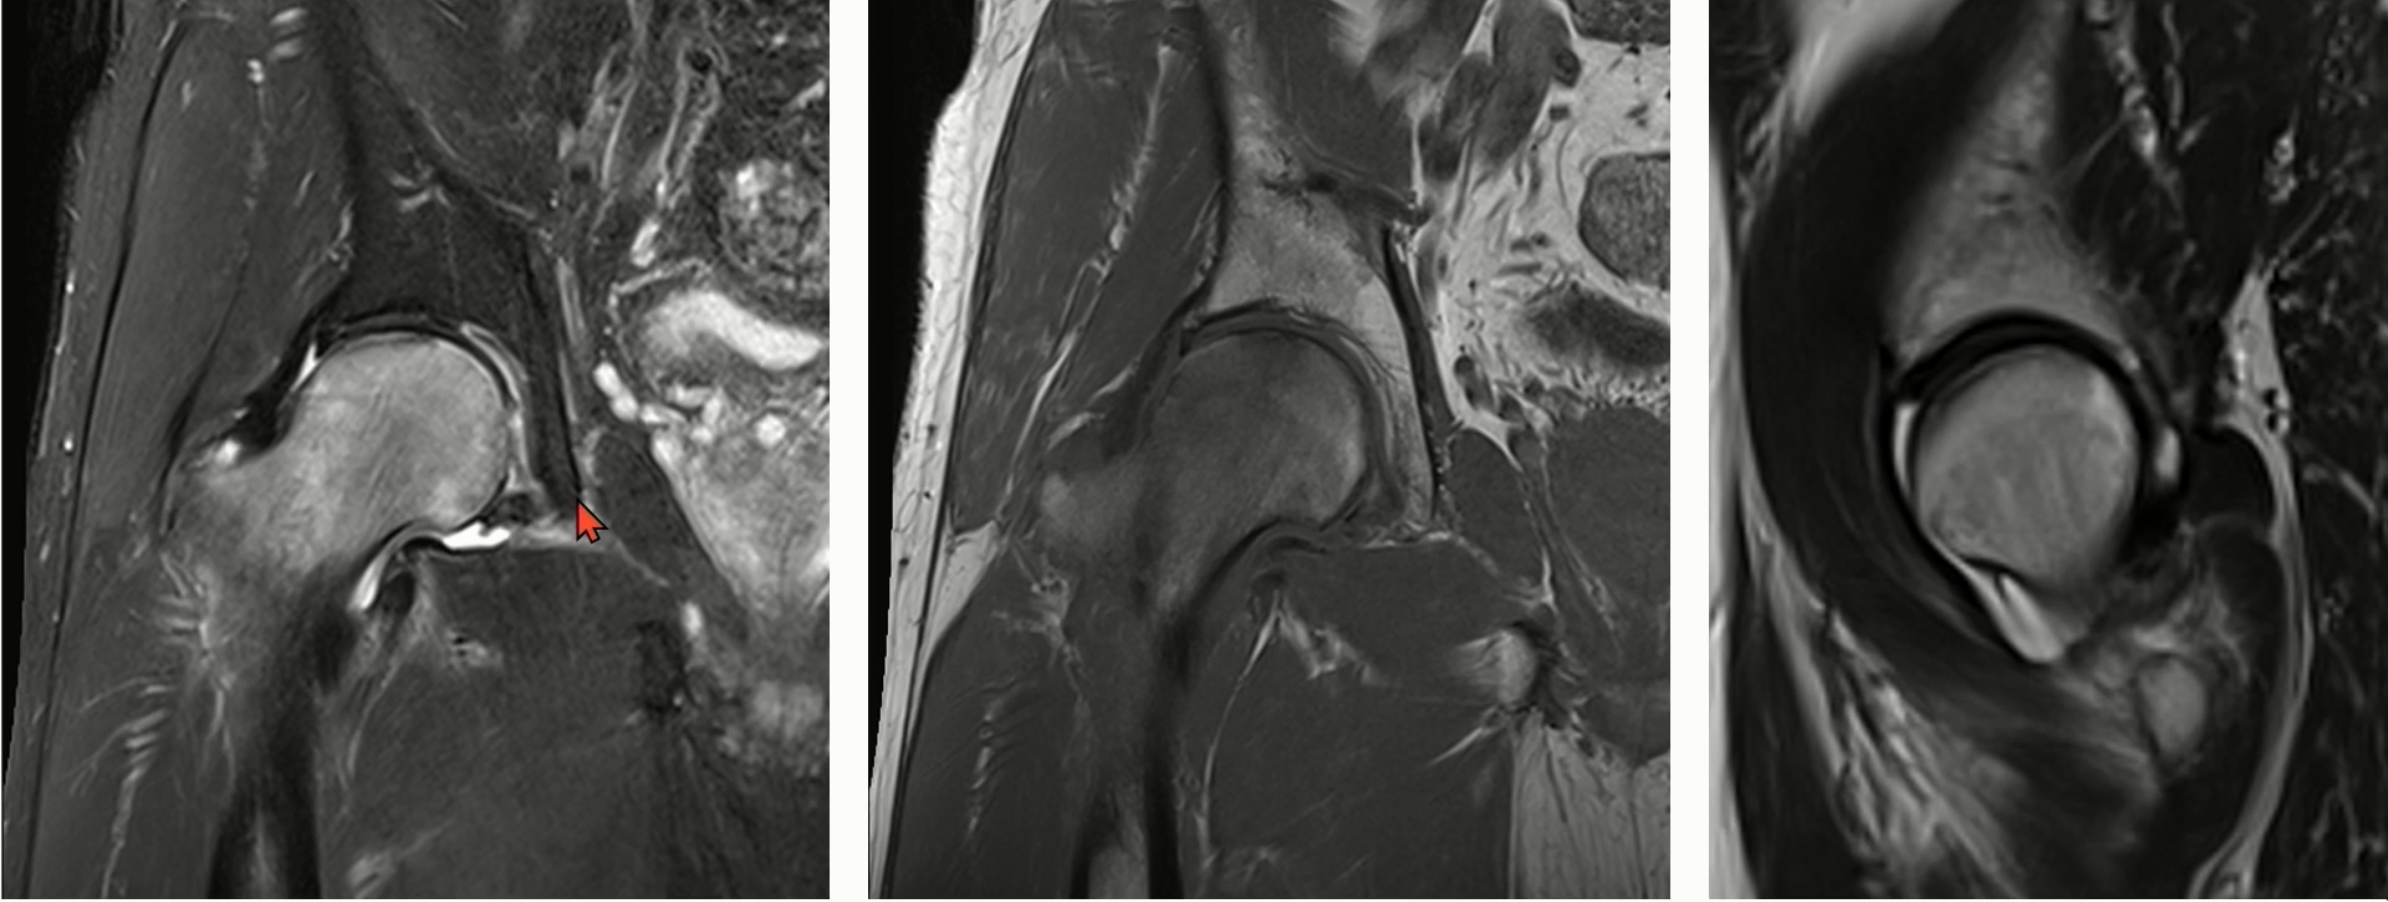

6. 대퇴골두 무혈성 괴사와 피로 골절의 감별점

좌측은 스트레스 골절, 우측은 골괴사입니다.